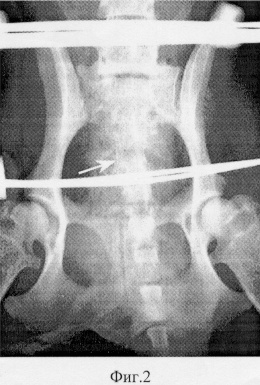

Фиг.3 – рентгенограмма таза животного после завершения лечения: а – прямая, б – боковая проекции.

На момент демонтажа аппарата рентгенологически выявлялась полная консолидация поврежденного крестца в анатомически правильном положении (фиг.3). Осложнений со стороны мышечно-связочного аппарата и внутренних органов таза не отмечалось. Животное активно передвигалось на всех четырех конечностях.